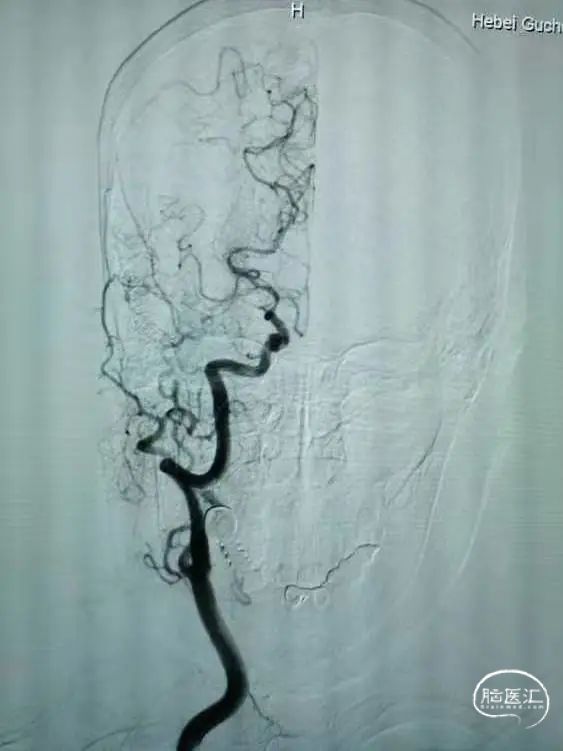

术前DSA的正位、侧位造影:

右侧颈内动脉DSA: